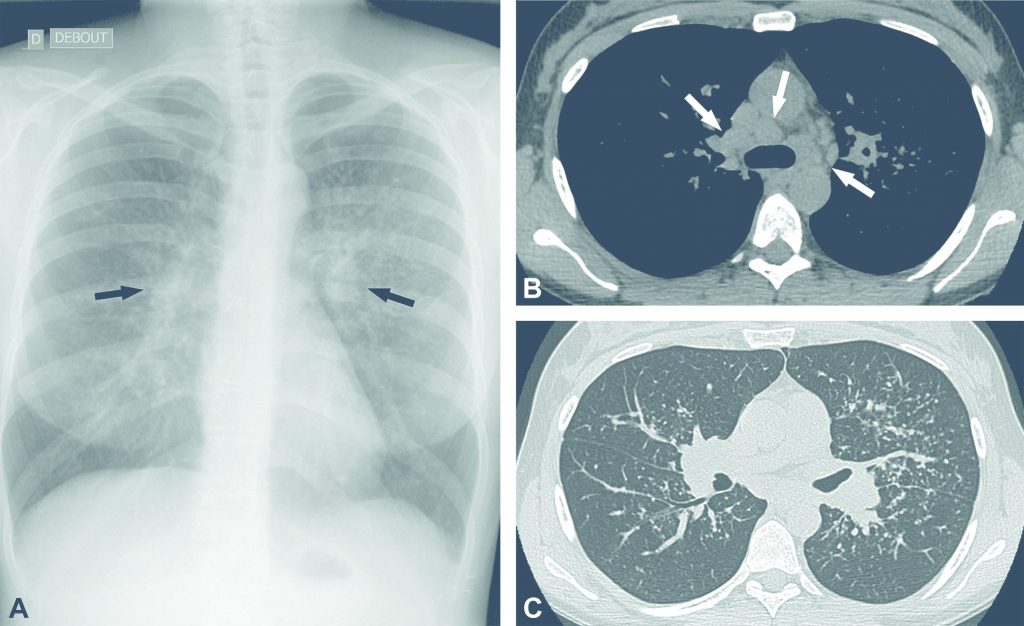

- stade 2 : adénopathies et atteinte interstitielle (figure 99.3) ; l’atteinte interstitielle se manifeste par un syndrome réticulonodulaire ;

Fig. 99.3. Sarcoïdose de stade 2.

La radiographie thoracique de face montre une hypertrophie des hiles pulmonaires liée à des adénopathies (flèches en A) et des anomalies parenchymateuses interstitielles. Le scanner thoracique non injecté réalisé chez le même patient montre les adénomégalies médiastinales et hilaires (flèches en B) ainsi que l’atteinte interstitielle pulmonaire à type de micronodules de distribution lymphatique (C).

Source : CERF, CNEBMN, 2022.